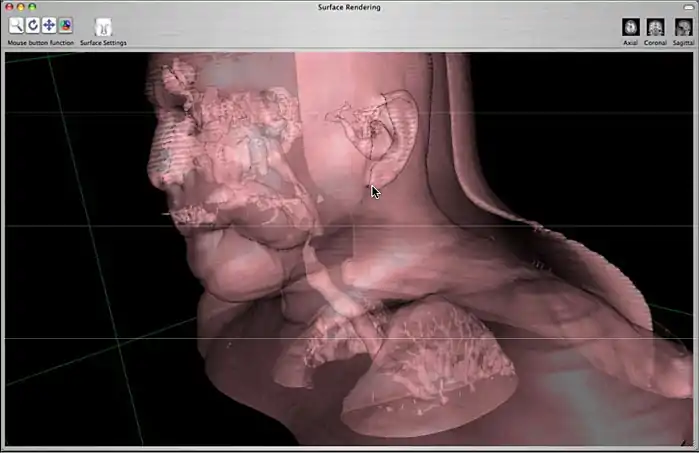

3) Surface Rendering

3D Surface Rendering

This reconstruction produces surfaces that are based on an “iso-contour” defined by the user. This technique is useful for virtual endoscopy and bone CTs. The user can define two different surfaces to render.